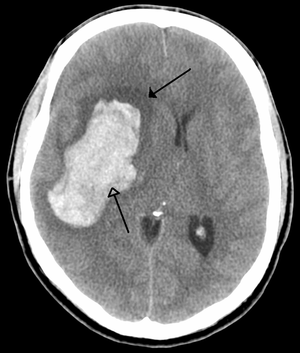

| CT scan slice of the brain showing a right-hemispheric ischemic stroke (الجانب الأيسر من الصورة). | |